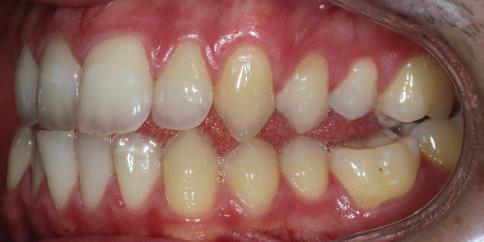

Dental Tribune Bulgarian Edition / октомври 2022 г.16 клиничен случай с алайнери Г орният латерален ре зец е вторият найчесто вродено липсващ зъб.1,2 Поради разполо жението му във видимата зона на усмивката лечение то на подобни случаи нала га мултидисциплинарен под ход, целящ отличен функцио нален и естетичен резултат. Налице са няколко лечебни мо далности, свързани с различ но разпределение на място то: първият вариант е орто донтско отваряне на място и възстановяване на липсва щия зъб с конструкция, под държана от съседните зъби3 или от имплант4, докато при втория подход разстоянията се затварят и премоларът заема мястото на канина.5 Изборът на лечебен подход трябва да бъде направен съв местно от зъболекар и паци ент въз основа на очакванията на последния и предвиди мостта на лечението. Множе ство фактори влияят върху това решение, като напри мер типа малоклузия, размера, формата и цвета на кучеш ките зъби6, оклузалните вза имоотношения (овърджет и овърбайт), лицевия профил, дължината на зъбната дъга и несъответствията в разме ра на зъбите.7 В настоящата публикация се разглежда случаят на жена в зряла възраст с вродена лип са на горен ляв латерален резец. Бяха приложени про зрачни алайнери за отваряне на място за единичен им плант и бяха постигна ти функционална оклузия и отлична естетика. ПРЕДСТАВЯНЕ НА СЛУЧАЯ Диагноза Пациентката бе на 32 годи ни, когато лечението започна, и първоначалното ѝ състоя ние бе следното (фиг. 1–3): липсващ горен ляв латерален резец; клас II, подклас I малоклузия; отклонение на горната сре динна линия вляво; Доклад на клиничен случай ЛЕЧЕНИЕ С АЛАЙНЕРИ НА ПАЦИЕНТ С АГЕНЕЗИЯ НА ЛАТЕРАЛЕН РЕЗЕЦ Д-р Iro Eleftheriadi и д-р Christodoulos Laspos, Гърция и Кипър Фиг. 1a–h Предоперативни лицеви и интраорални снимки. Фиг. 2a–e Дигитални модели преди началото на лечението. Фиг. 3 Панорамна снимка преди лечението. Фиг. 1a Фиг. 1d Фиг. 1f Фиг. 2a Фиг. 2d Фиг. 2b Фиг. 2e Фиг. 3 Фиг. 2c Фиг. 1b Фиг. 1e Фиг. 1g Фиг. 1h Фиг. 1c

Dental Tribune Bulgarian Edition / октомври 2022 г. 17клиничен случай с алайнери леко струпване в долната че люст; несъответствие по Болтън (мандибуларен излишък от 3.06 мм във фронталната зона и общо 1.47 мм); издължено лице с лицева аси метрия; конвексен профил с ретруди рана долна челюст и проми нентен нос. На мястото на зъб #46 бе на лице имплант, а зъби #16 и 26 са ендодонтски лекувани. Тези зъби бяха асимптоматич ни, затова бе взето решение да се прави релечение само при нужда. Мъдреците липсваха. Анализът на телерентгеногра фията (фиг. 4) показа ретрог натна мандибула (SNB: 74.2°) и нормална инклинация на резците както в

Цели на лечението и лечебен план Целите на лечението бяха следните: нивелиране и подреждане на зъбите и в двете зъбни дъги; отваряне на пространство за липсващия латерален резец; коригиране на отношенията при канините и моларите до клас I; и корекция на отклонението на срединната линия. Лечебният план включваше: корекция на отношенията при кучешките зъби и мола рите до клас I с дистализира не на максилата; отваряне на пространство в областта на #22 за поставя не на единичен имплант; корекция на срединната ли ния; и създаване на място за раз ширяване на зъб #12 и апрок симална редукция в долната челюст с цел подобряване на несъответствието по Болтън и осигуряване на подобра оклузия. Изпълнение на лечебния план Този случай бе изпълнен със системата за алайнери Invisalign (Align Technology). Одобреният първоначален лечебен план предвиждаше 49 алайне ра с дистализиране на задни те горни зъби до клас I (прибли зително с около 3.5 мм; фиг. 5). За бъдещия имплант в областта на липсващия латерал бе планирано пространство от 6.5 мм, докато във фронталния сегмент на долната челюст бе предвидена апроксимална редук ция. В дясната страна бутон за ластици клас II бе поставен на зъб #47 вместо на зъб #46, за да не се увреди короната на импланта. Понеже пациентката жи вееше в чужбина,

следните казуси: недобра оклу зия в дисталните зони по вре ме на дистализирането на гор ната челюст и накланяне на зъб #21 (фиг. 7). Последното се дължи на липсата на компози тен атачмънт на този зъб, каквото не бе зададено в пър Фиг. 4 Телерентгенография и цефалометричен анализ преди началото на лечението. Фиг. 5a–e Одобреният първоначален лечебен план. Фиг. 6a–h Снимки по време на лечението, показващи нуждата от внасяне на някои корекции. Фиг. 4 Фиг. 5a Фиг. 5d Фиг. 6a Фиг. 6d Фиг. 6f Фиг. 6b Фиг. 6e Фиг. 6g Фиг. 6h Фиг. 6c Фиг. 5e Фиг. 5b Фиг. 5c

Dental Tribune Bulgarian Edition / октомври 2022 г.18 воначалния план. Тези пробле ми бяха адресирани чрез допъл нителна поръчка на алайнери с торк контрол и зададено екст рудиране на задните зъби с цел установяване на добри оклузал ни контакти в дисталните об ласти, като бяха предвидени и оптимизирани атачмънти с контрол над корените за корекция на ангулацията на макси ларните резци (фиг. 8). Резултати от лечението Панорамната рентгено графия след ортодонтското лечение показа благоприятна паралелна позиция на съседни те зъби, подходяща за поставя не на имплант в областта на #22, както и конвергенция на ко рените на зъби #44 и 45 (фиг. 9), но преценихме, че няма да от деляме допълнително лечебно време за коригирането ѝ поради факта, че пациентката бе мно го доволна от постигнатия до момента резултат. След при ключване на лечението бяха постигнати отлични взаимо отношения клас I при мола рите и канините, а срединни

съвпадаха. Върху им

планта бе поставена временна коронка (фиг. 10 и 11), докато бъде изготвена окончателна та. Бе постигнат отличен кра ен резултат. Меките тъка ни около импланта напълно заздравяха, което доприне се за перфектната хармония между бяла и розова естетика (фиг. 12–15).